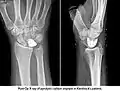

Fig 2. Kienbocks x-ray

Kienbock’s Disease is defined as avascular necrosis of the lunate (Cross & Matullo, 2014, p. 141). The direct cause of Kienbock’s disease is largely unknown (Almquist, 1986, Nathan & Meadows, 1987) however, studies have confirmed an association between negative ulnar variance and the development of Kienbock’s Disease (Bonzar et al., 1998, Mirabello, Rosenthal, & Smith, 1987). Subjective information shows that ROM tests and palpation cause the patient a large amount of pain. It was identified that the most comfortable position for the client to be in is a supported, resting position. This is supported by Rizzo (2008, p. 491) by stating that avascular necrosis of the carpus is an important cause of wrist pain, limited motion, and weakness.

The symptoms of Kienbock’s disease include; generalised or focal wrist pain, increased wrist stiffness and pain on flexion or extension, decreased grip strength, and limited range of motion (Alexander & Lichtman, 1986, Beckenbaugh, 1980, Laframboise, Gringmuth, & Greenwood, 2012). Laframboise et al., (2012) suggests that Kienbock’s disease presents with symptoms alike a sprain of the scapho-lunate ligament or a lunate fracture or dislocation.